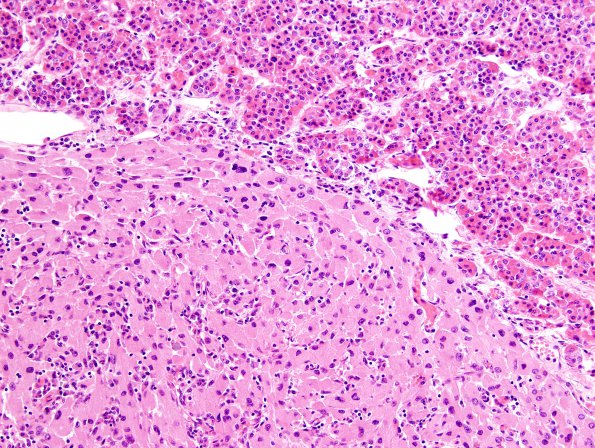

1A2-4 The junction of the adenohypophysis and GCT at three different magnifications (H&E) The GCT does not resemble the normal adenohypophysis.